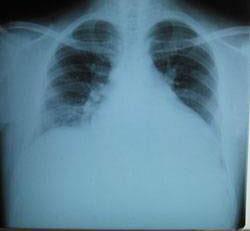

摘要:關(guān)于擴張性心肌病的最新治療,小巷深處的隱藏寶藏正逐漸為人們所發(fā)現(xiàn)。通過先進的醫(yī)療技術(shù)和方法,擴張性心肌病的治療取得了新的進展。這些治療方法旨在改善心臟功能,提高患者生活質(zhì)量。小巷深處的醫(yī)療機構(gòu)或?qū)<铱赡茈[藏著寶貴的治療經(jīng)驗和方法,為尋求最佳治療方案的病患帶來希望。更多詳細信息需要進一步探索和研究。

擴張性心肌病是一種嚴重的心臟疾病,但“心之港灣”為你帶來希望,這里的專家團隊一直在深入研究擴張性心肌病的最新治療方法,并深知每位患者都渴望得到最佳的治療和關(guān)懷,他們努力不懈,為患者帶來生機和新生。

你將了解到最新的藥物治療、心臟康復計劃以及生活方式調(diào)整等方面的知識?!靶闹蹫场边€開展了一系列臨床試驗,為患者提供最新的治療方案,他們的治療方法全面且個性化,因為每個患者的狀況都是獨特的,所以需要因人而異定制治療方案。